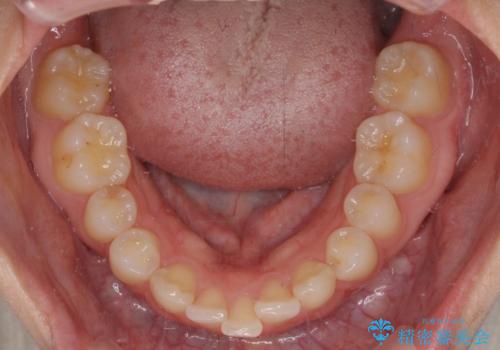

- 前歯の歯並びと神経を取って変色してしまった前歯を気にして来院された患者様です。

上下前歯の歯列不正はインビザラインにより整え、その後に、前歯2本をオールセラミッククラウンにて補綴治療することとしました。

下顎前歯が1本欠損しており、下顎歯列の大きさが本来よりも小さいため、上顎歯列とのバランスが悪く、深い咬み合わせになっていました。

上顎にIPRを多用して歯列の大きさを小さくするよう試みましたが、理想的な咬み合わせまでには改善させることはできませんでした。